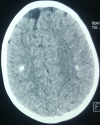

Cranial CT scan demonstrating bilateral supra-tentorial and sub-ependymal and cortical calcifications

We describe a three-year-old boy who had a growth and psychomotor retardation associated with inappropriate lack of thirst and vasopressin secretion in the presence of chronic plasma hyperosmolarity. Computed brain tomography revealed bilateral supratentorial sub-ependymal and cortical calcifications. Dissociation in the plasma vasopressin response to osmotic change was demonstrated in this patient. Treatment with a vasopressin analogue, desamino-D-arginine vasopressin (DDAVP) and forced intake of water restored plasma osmolality and serum sodium levels to normal.